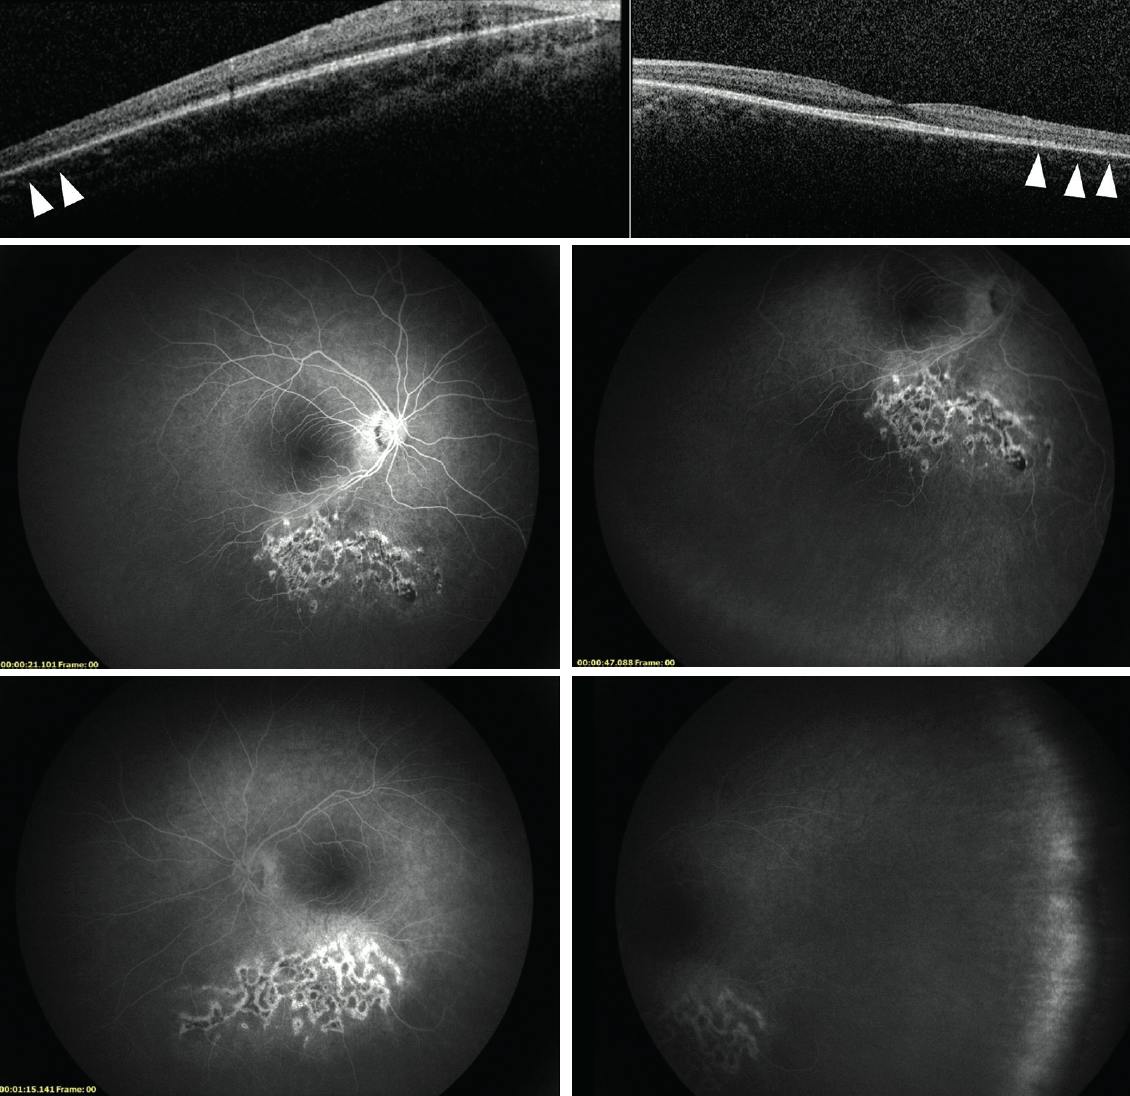

On initial examination, his BCVA was 20/30 OD and 20/40 OS. The anterior segment examination was unremarkable in each eye. The posterior segment was remarkable for an area of preretinal fibrosis along the inferior arcade in the right eye and symmetric extramacular pigmentary changes located at the inferior retina in each eye (Figure 1). During an examination under anesthesia, A- and B-scan demonstrated the axial length to be 23.9 mm in the right eye and 22.5 mm in the left eye.

OCT showed marked thinning of the retina, especially the outer layers, correlating with areas of abnormal pigmentation (Figure 2). Fluorescein angiography showed staining of the chorioretinal lesions in each eye, as well as peripheral nonperfusion, mostly temporally (Figure 2). An electroretinogram showed significant rod and cone dysfunction, which was suggestive of a recessive cone-rod dystrophy or retinitis pigmentosa (RP)–related retinopathy. Initial genetic testing obtained elsewhere was negative for RP, fragile X syndrome, and other genetic conditions.